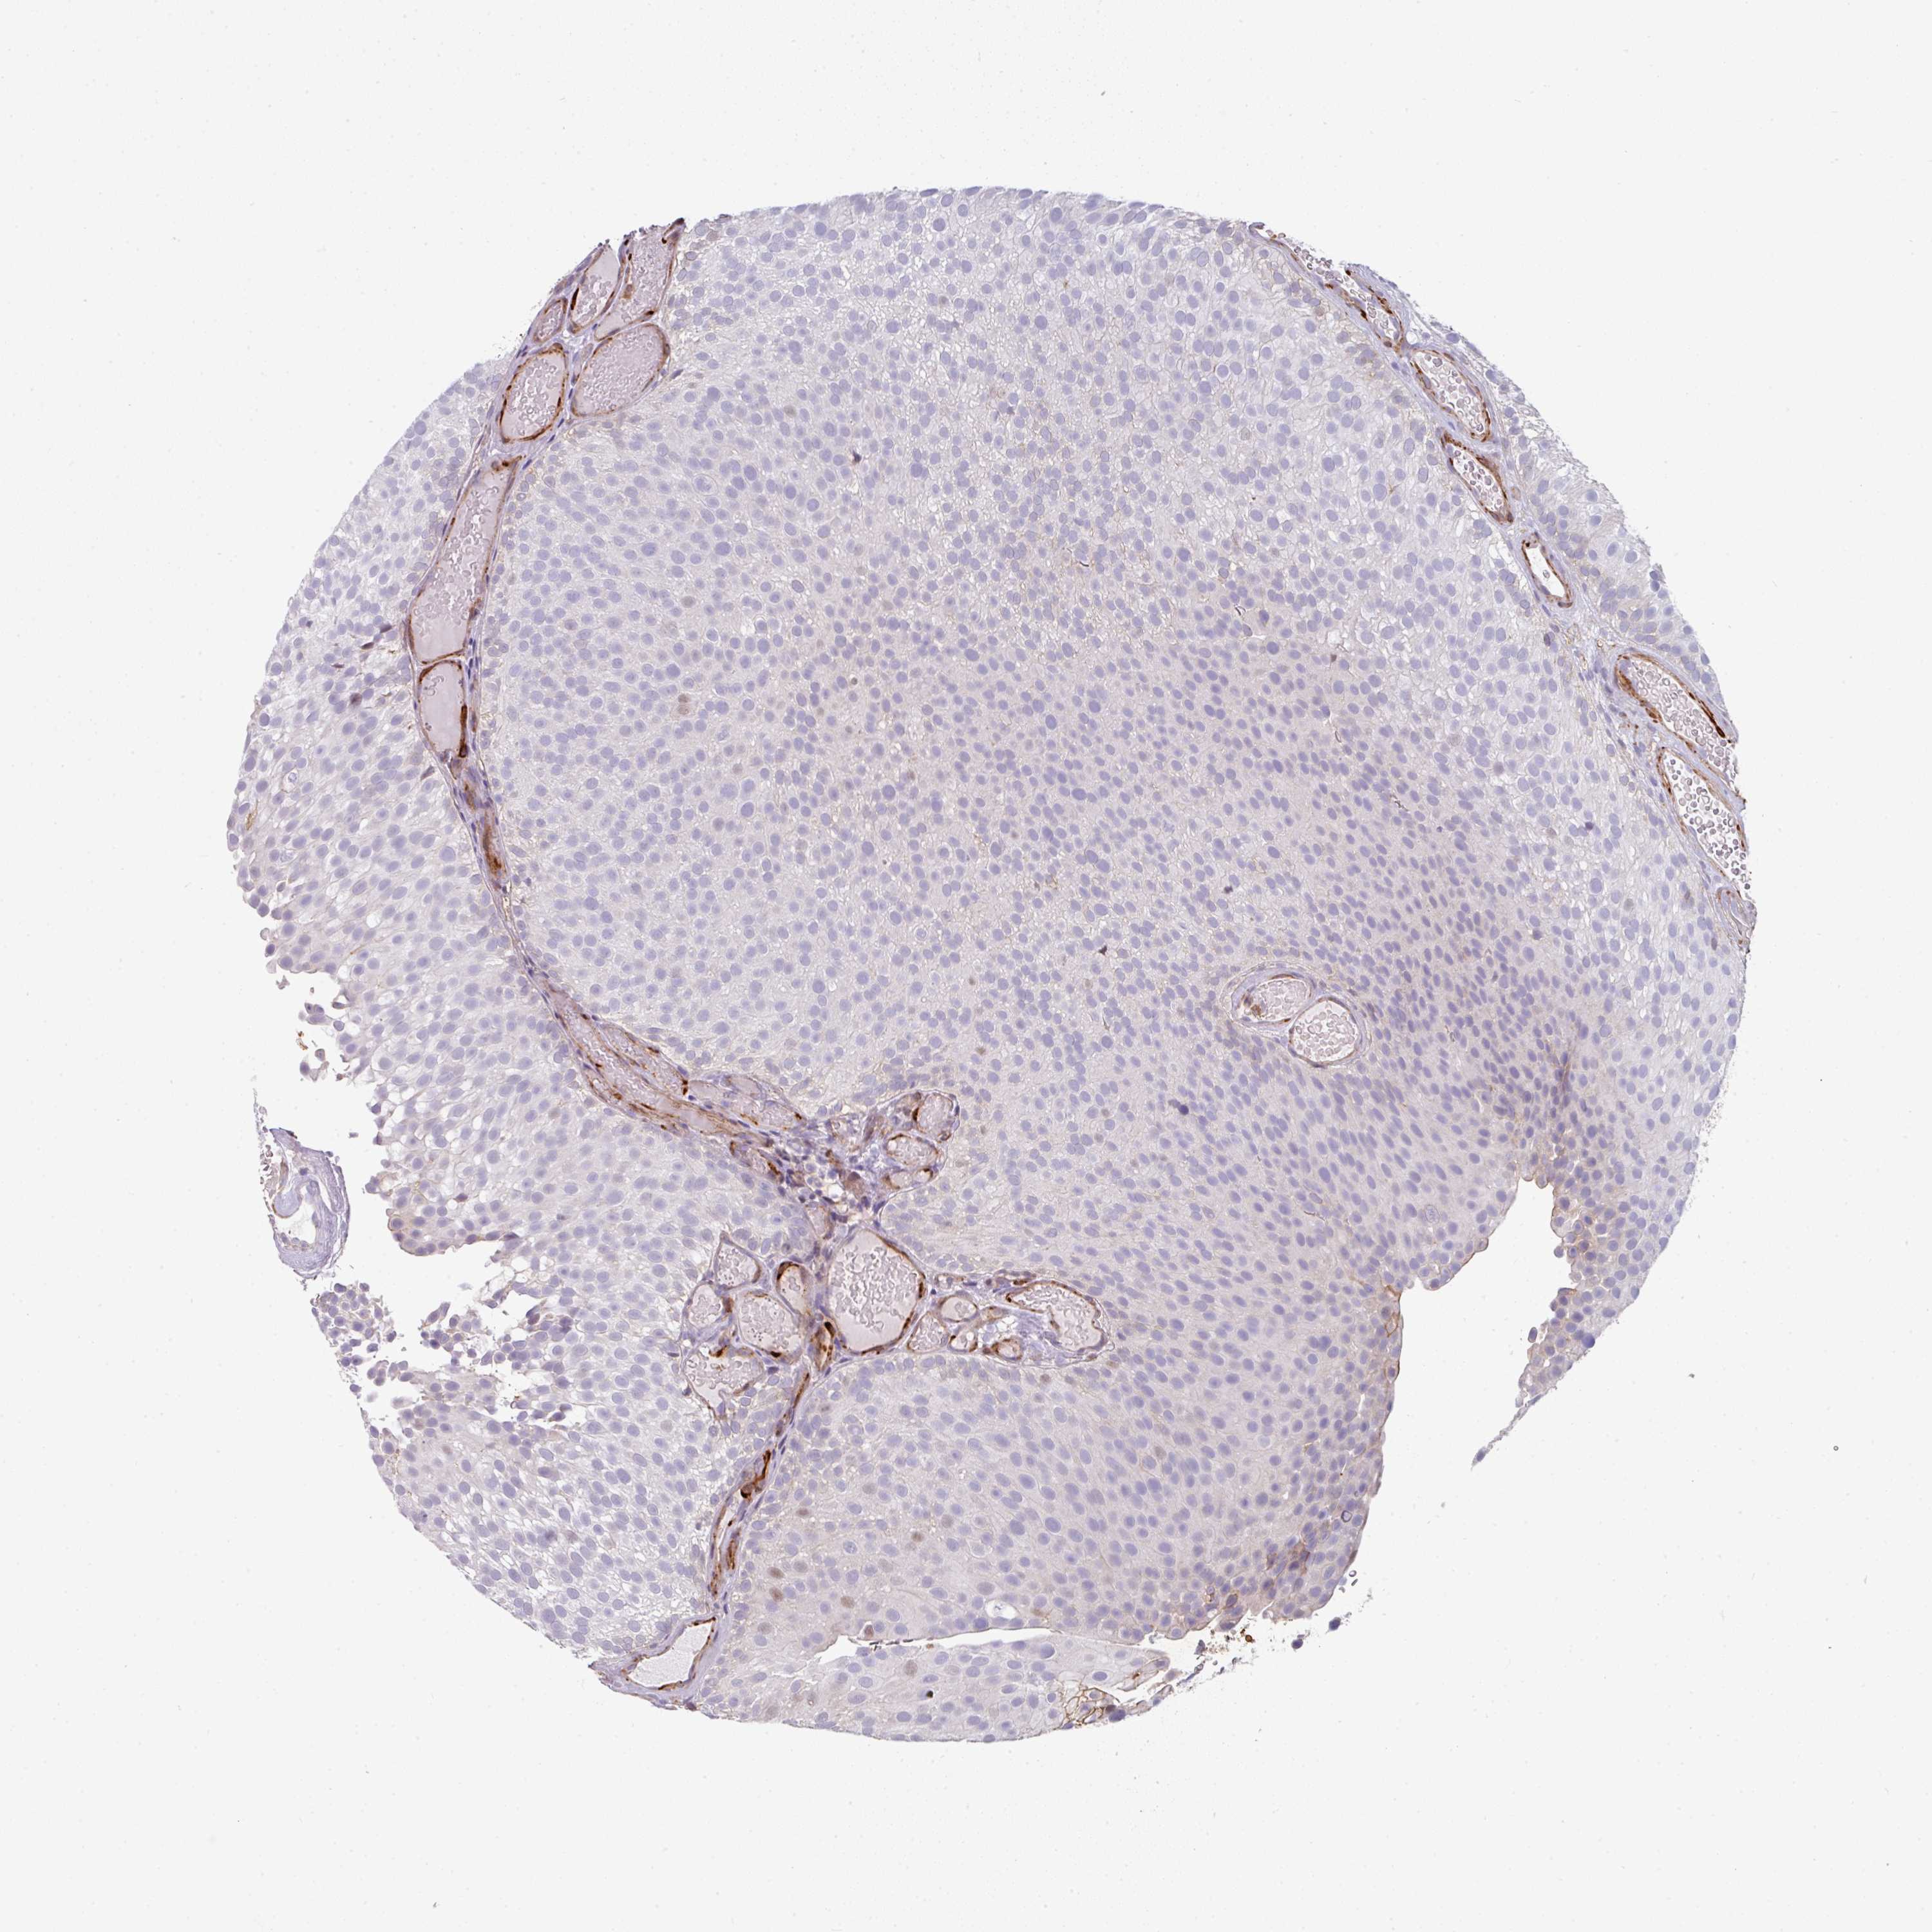

UROTHELIAL CANCER - Protein expressioni

A mouse-over function shows sample information and annotation data. Click on an image to view it in a full screen mode. Samples can be filtered based on level of antibody staining by selecting one or several of the following categories: high, medium, low and not detected. The assay and annotation is described here.

Antibody stainingi

Antibody staining in the annotated cell types in the current human tissue is reported as not detected, low, medium, or high, based on conventional immunohistochemistry profiling in selected tissues. This score is based on the combination of the staining intensity and fraction of stained cells.

Each image is clickable and will lead to virtual microscopy that enables deeper exploration of all samples and also displays staining intensity scores, fraction scores and subcellular localization as well as patient and tissue information for each sample.

Antibody HPA054347

Antibody HPA058007

Urothelial carcinoma, High grade

Urothelial carcinoma, NOS

Urothelial carcinoma, Low grade